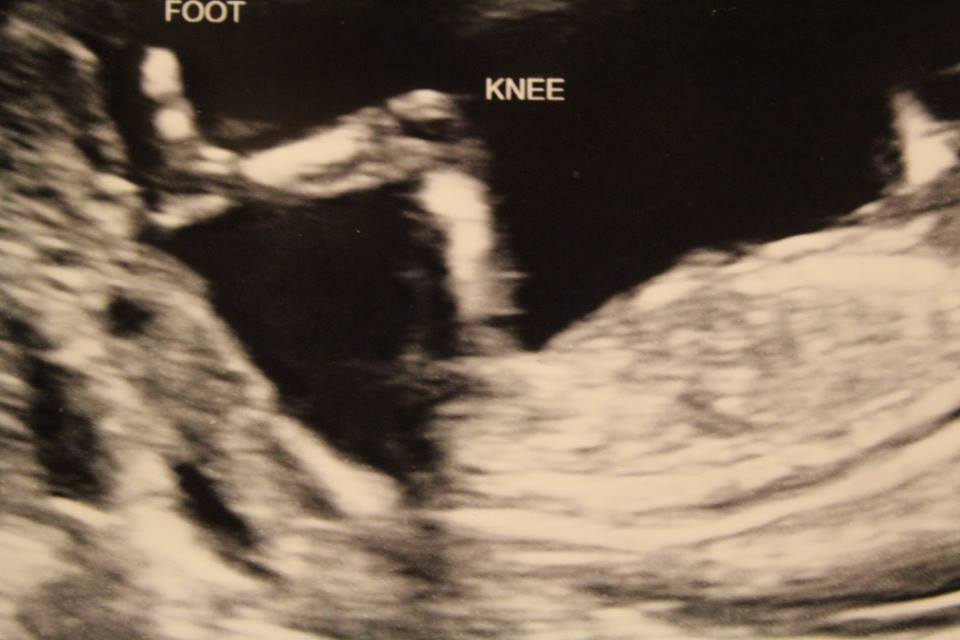

I've had mostly girl guesses elsewhere but then I've been told that there isn't any nub. After five boys in a row I'm afraid to get my hopes up. Is there a nub to be seen? Thanks so much to anyone who takes a look!